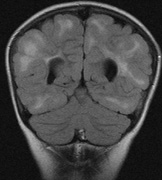

Mental retardation and seizures in TSC are often associated with benign CNS astrocytic hamartomas.131 On imaging, the cerebral lesions show three patterns:132

1. Superficial cortical sclerosis (parenchymal hamartoma) which distort the gyri. Microscopy shows large atypical fibrillary type astrocytes with few associated neurons and areas of calcification.133 The numerous abnormal glial processes and fibers make the tissue abnormally firm or “sclerotic” on palpation (Fig. 13).132

2. Subependymal nodules (SEN) are typically found along the lateral borders of the ventricles and parehncymal brain lesion (“cortical tubers”) (Figs. 14 and 15). Calcification in the first year of life is rare.132

On MRI imaging, the subependymal nodules and parenchymal brain lesions of infants (age ≤3 months) and adults show different signal characteristics. Infant CNS tubers are hyperintense on T1-weighted images and hypointense on T2-weighted images, which is the opposite of the pattern seen in adults.134 Malignant transformation of SEN occurs in about 10% to 15% of patients and the resultant subependymal giant cell astrocytoma accounts for 25% of premature deaths in TSC.135,136

Fig. 15. Tuberous Sclerosis Complex. (a) Patient 1: Axial CT scans demonstrating typical calcification of subependymal nodules in a 13-year-old girl with a history of seizures. (b and c) Patient 2. (b) Axial T2-weighted images demonstrate calcified subependymal nodules (arrowheads) and cortical tubers typical of tuberous sclerosis. (c) Widespread cortical tubers are seen on a coronal FLAIR sequence as thickening of the cortex and high signal of the subcortical white matter.